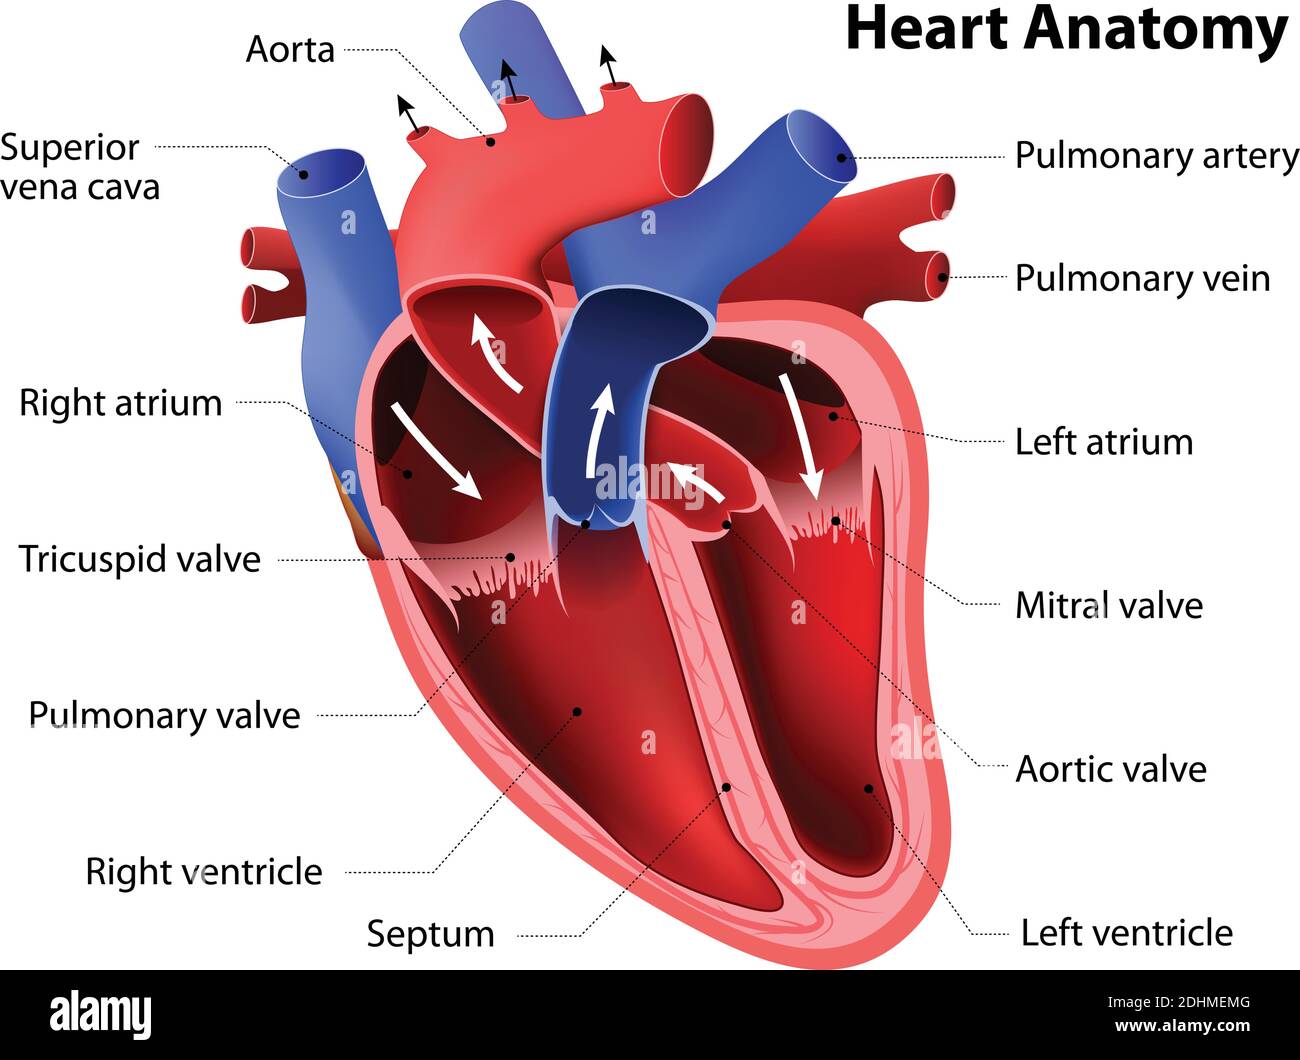

Anatomy of the human heart. Cross sectional diagram of the heart with main parts labeled. Human heart diagram Vector illustration. Educational diagram Stock Vectorhttps://www.alamy.com/image-license-details/?v=1https://www.alamy.com/anatomy-of-the-human-heart-cross-sectional-diagram-of-the-heart-with-main-parts-labeled-human-heart-diagram-vector-illustration-educational-diagram-image551609872.html

Anatomy of the human heart. Cross sectional diagram of the heart with main parts labeled. Human heart diagram Vector illustration. Educational diagram Stock Vectorhttps://www.alamy.com/image-license-details/?v=1https://www.alamy.com/anatomy-of-the-human-heart-cross-sectional-diagram-of-the-heart-with-main-parts-labeled-human-heart-diagram-vector-illustration-educational-diagram-image551609872.htmlRF2R1C00G–Anatomy of the human heart. Cross sectional diagram of the heart with main parts labeled. Human heart diagram Vector illustration. Educational diagram

heart anatomy. Part of the human heart Stock Vectorhttps://www.alamy.com/image-license-details/?v=1https://www.alamy.com/heart-anatomy-part-of-the-human-heart-image389527840.html

heart anatomy. Part of the human heart Stock Vectorhttps://www.alamy.com/image-license-details/?v=1https://www.alamy.com/heart-anatomy-part-of-the-human-heart-image389527840.htmlRF2DHMEMG–heart anatomy. Part of the human heart